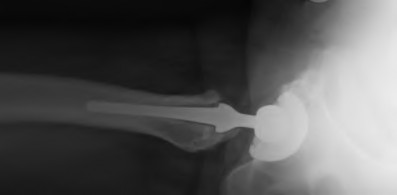

An 82-year-old woman falls and sustains the fracture shown in figure A. She denies any history of dislocation or prodromal pain prior to her fall. What is the most appropriate treatment?

The radiograph demonstrates a periprosthetic femur fracture extending to the tip of the stem. The long spiral fracture is consistent with a loose implant. The bone stock is sufficient. Therefore, this fracture pattern would classify as a B2 using the Vancouver classification system. The Vancouver classification for periprosthetic femoral fractures is simple yet incorporates all the pertinent factors such a location, stem fixation, and bone stock. Type A is a trochanteric fracture- lesser or greater. These can be treated non-operatively usually and ORIF if symptomatic. Type B fractures are around or just below the stem and are subdivided into three types. Type B1 is a fracture with a well fixed stem.

The treatment is cable plating or allograft struts or a combination of the two. Type B2 is a fracture with a loose stem with good bone stock. The treatment is a cementless porous coated long stem atleast two diameter length past the

fracture site. Type B3 is a fracture with a loose stem and comminution. For younger patients, use cementless porous coated long stems with allograft struts. For older patients, consider a tumor prosthesis. Cement fixation is sometimes necessary Type C is a fracture well below the stem tip. These can be treated independently of the prosthesis.

Springer et al showed optimal outcomes with revision involving long extensively-coated femoral stems for Vancouver B fractures.

Masri et al review the classification and treatment of periprosthetic femur fractures.